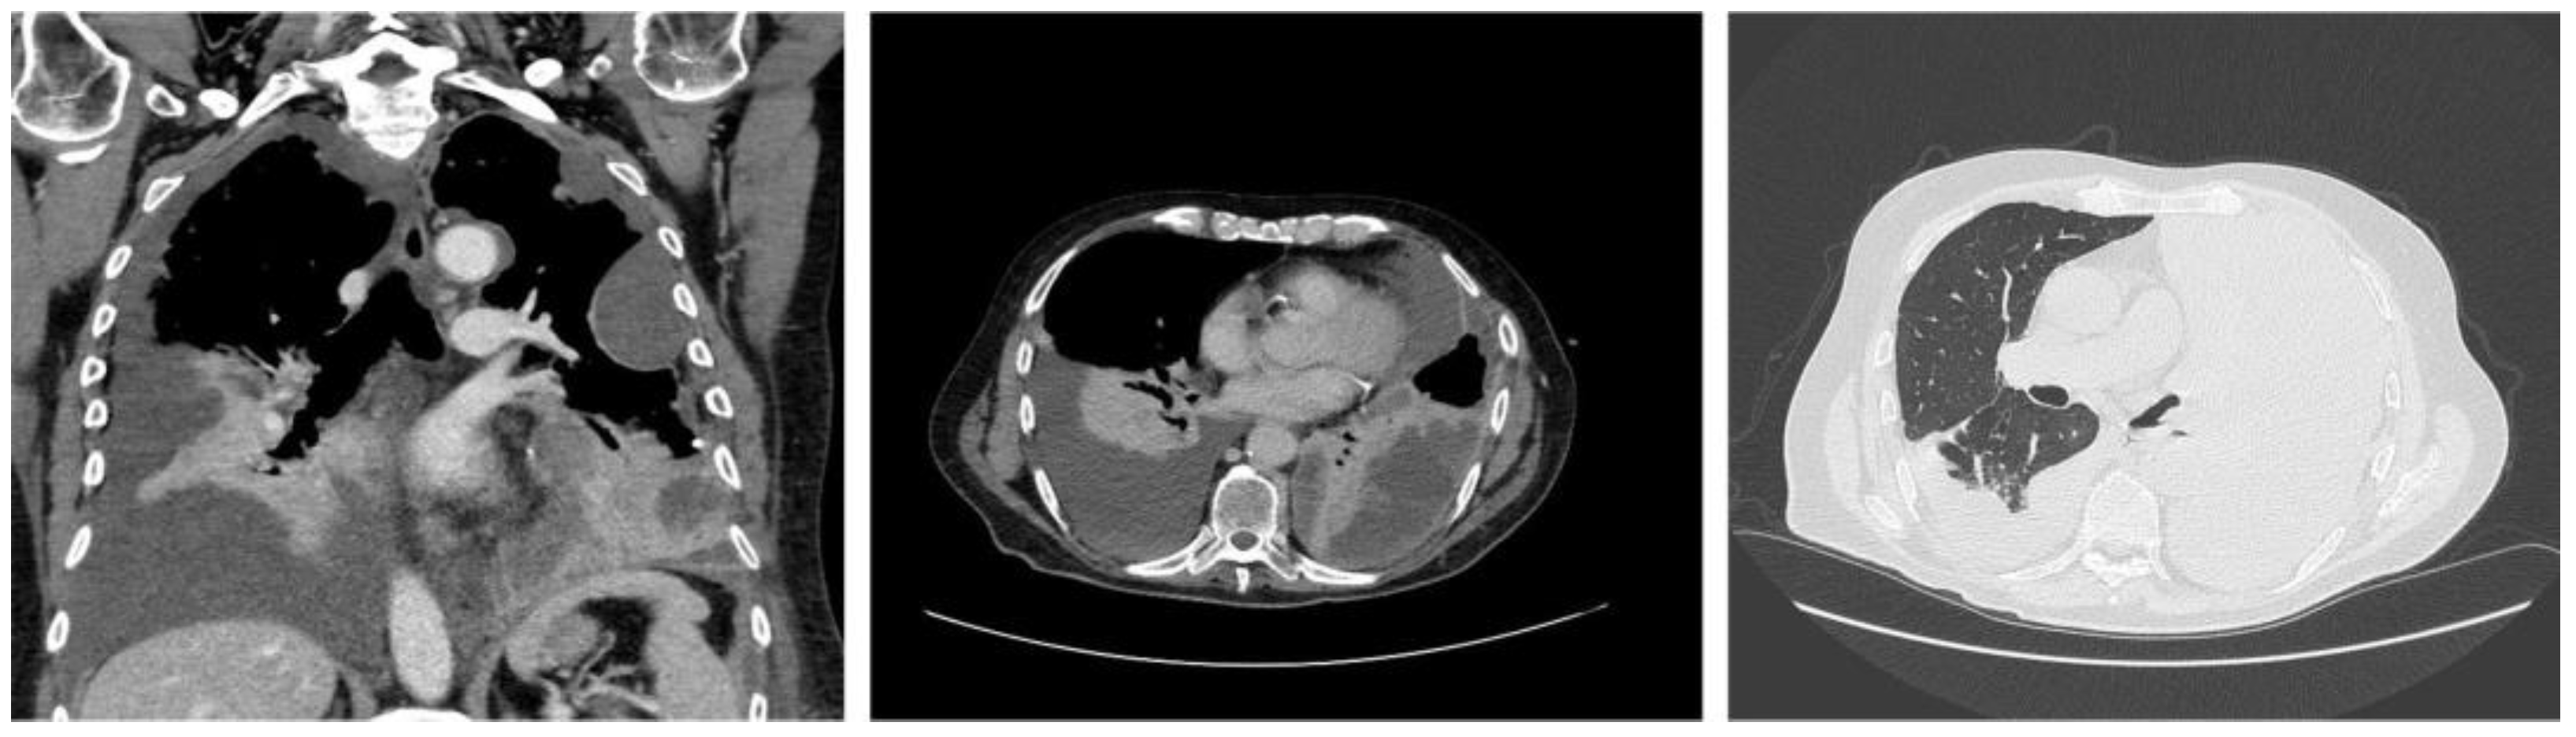

2. Case Report